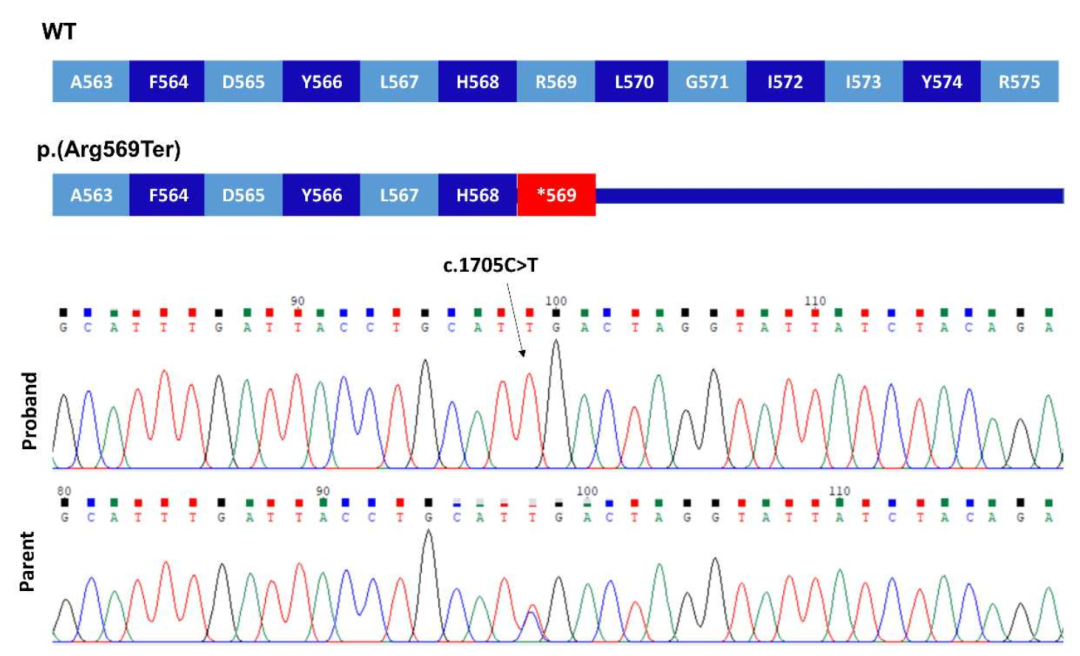

在家族1中,通过WGS和Sanger测序在3个患有椎体-骺端发育不良 (Spondylometaphyseal dysplasia, SMD)的兄弟中发现了一个纯合子致病突变PRKG2 (NM_006259.3:c.2282dup, p.Asp761Glufs*34)。有趣的是,F1-IV-6患者 (中度致病)也有I型成骨不全 (Type I osteogenesis imperfect, OI)。一项早期临床外显子组测序研究发现,在分子诊断的病例中,有4.6%的病例有一个以上的基因变异导致混杂 (Blended)表型。

在家系2中,一个患有肢端发育不良的女孩的外显子组测序显示了一个纯合子致病变异PRKG2c.1705C>T;(Arg569*)。将F2-V-3的基因组数据与之前发表的病例进行比较,未能检测到PRKG2基因座 (Locus)上共有的单倍型。c.1705 C>T的复发似乎更有可能是由于单独的突变事件。

这里描述的这两种变异都非常罕见,gnomAD数据库中没有p.Asp761Glufs*34,而p.Arg569*为单基因。在这两个家系中,致病变异都存在于较大的ROHs中。虽然p.Arg569*突变已经被证明影响下游的MAPK途径,但家系1中的p.Asp761Glufs*34很可能也是有害的,因为蛋白C末端Asp>Phe及33个氨基酸发生替换。在计算机建模中的研究突出了该区域的结构重要性,特别是终末Phe762残基。

为了从功能上证实新发现的p.Asp761Glufs*34变异的致病性,我们首先用Western blot分析了cGKII的表达。以先前鉴定的p.Arg569*突变作为阳性对照,在这两个突变中,cGKII被检测到的大小与预测的大小一致,尽管与野生型相比,cGKII的水平显著降低 (≥80%)。接下来,我们通过分析p.Asp761Glufs*34突变体诱导Raf-1在Ser-43和ERK1/2磷酸化的能力,评估了它是否能够抑制FGF2诱导的MAPK通路。结果显示,p.Asp761Glufs*34突变体未能在Ser-43处磷酸化Raf-1,因此降低了FGF2诱导的ERK1/2磷酸化,这与p.Arg569*变体的结果相似。

PRKG2变异对cGKII蛋白水平/MAPK通路调控的影响